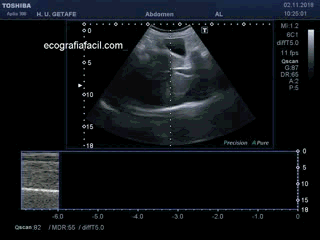

La colocación de la/el paciente, como buscamos el lugar idóneo donde la cámara líquida o lo que vaya a ser pinchado y cómo marcar el lugar correcto.

The placement of the patient, as we look for the ideal place where the liquid chamber or what is going to be punctured and how to mark the right place.

Finalmente y como método de estudio del diafragma, tenemos la representación en modo M donde vemos como colocar el roi lineal de puntos que mide la actividad del diafragma con la respiración y su representación como una línea curva en la gráfica mostrando el movimiento de dicho músculo en ese punto concreto.

Finally and as a method of studying the diaphragm, we have the M-mode representation where we see how to place the linear roi of points that measures the activity of the diaphragm with the breath and its representation as a curved line in the graph showing the movement of that muscle in that particular point.